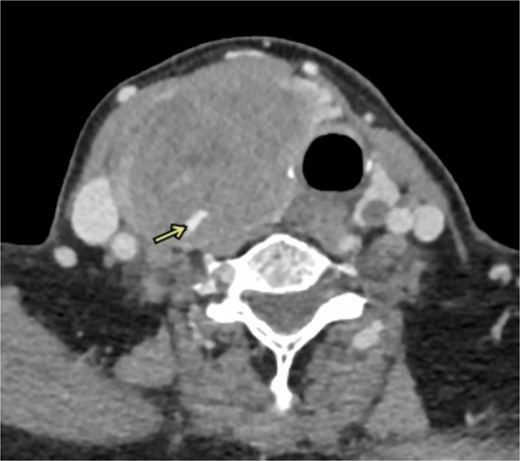

This case study describes a 76-year-old female with a history of type 2 diabetes and hypertension for fifteen years, controlled by her medication. She was swimming when she noted a sudden swelling in her neck. She presented to the emergency department of our hospital with right neck swelling for one-day duration. Physical examination shows a vitally stable patient with a localized neck mass not movable with swallowing and not associated with compressive symptoms. Computed tomography (CT) scan showed significant enlargement of the right thyroid lobe with heterogeneous predominantly hyperdense mass with mass effect on the airway with leftward deviation of the trachea (Fig. 1). Pre-operative CT Angiography showed active extravasation (Fig. 2). Also, there is a suspected right thyroid artery arching over the hematoma. The appearance of the artery raised the possibility of this artery being the cause of the hematoma. Then, a diagnostic angiogram was performed, which showed a dilated, ectatic-looking superior thyroid artery with flow into the hematoma, confirming the source of the hematoma. The patient successfully underwent angioembolization and hematoma evacuation without complications. During the procedure, an unexpectedly large solid component resembling thyroid tissue and a sac surrounding the hematoma were found. The patient was admitted to the Surgical Intensive Care Unit for post-operative monitoring and to prevent potential airway obstruction. The resected specimen was sent for further evaluation by pathology. Gross examination shows large dark brown hemorrhagic mass with thyroid tissue identified measuring 7.5 cm × 0.5 cm. Histopathology examination of the specimen revealed thyroid tissue with extensive hemorrhage and irregular dilated vascular spaces, as well as capillary-like vessels present in thyroid parenchymal tissue. Few thick-walled blood vessels were seen. These vascular channels are lined by bland endothelial cells (Fig. 3A, B). No cellular atypia, mitosis or solid growth pattern was observed. The vascular lining is diffusely positive for CD34, CD31, D2–40, and FLI1 (Fig. 3C, D). Given the above features of histopathology and immunohistochemistry studies, the diagnosis was compatible with primary thyroid hemangioma. Five months post-surgical resection, the patient’s follow-up indicates that she is in good health with no neck swelling, hoarseness of voice, or difficulty tolerating a regular diet. Her wound has healed without any signs of infection.

Coronal imaging of the unenhanced CT shows a large right thyroid lobe heterogeneous mass measuring 9.2 cm × 5.2 cm × 5.5 cm with mass effect on the airway and tracheal displacement to the left.